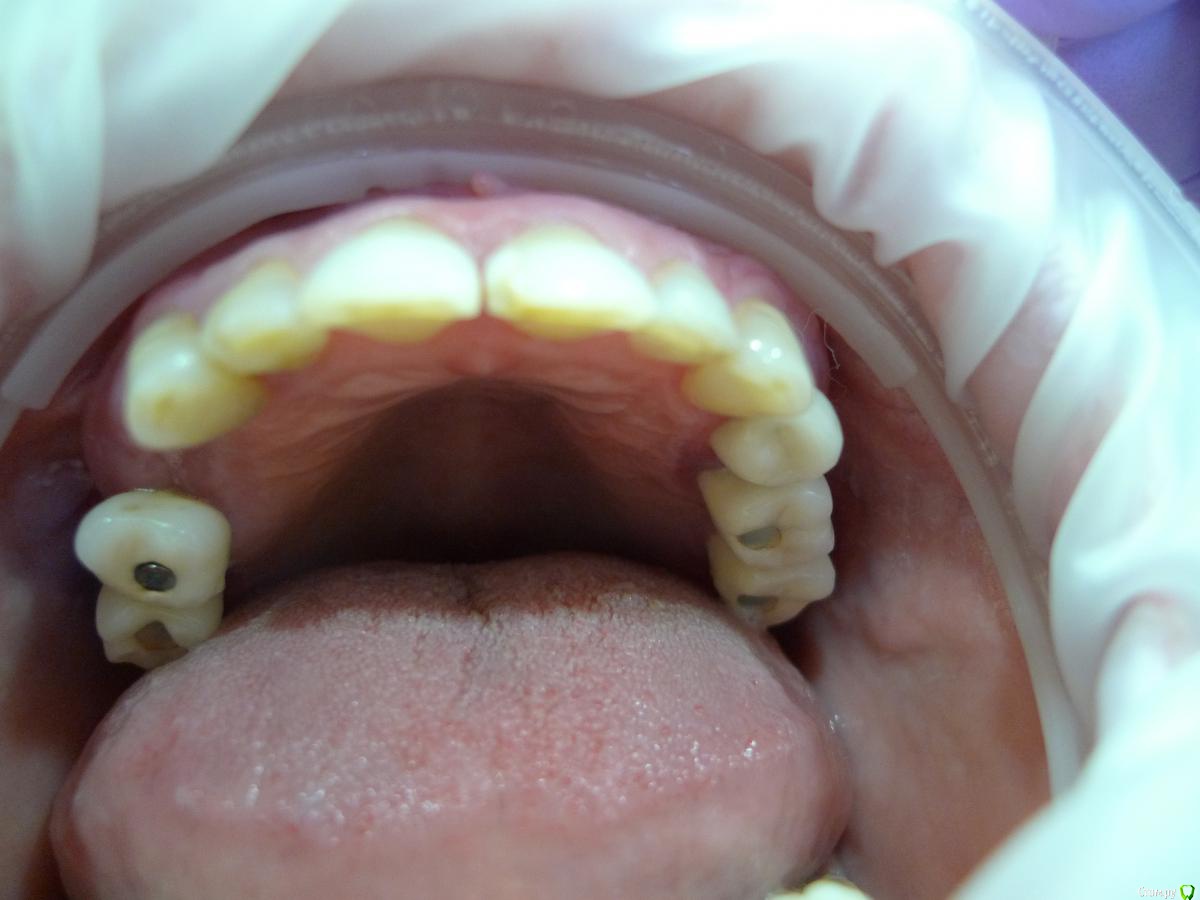

alekszander Опубликовано 26 февраля, 2016 Автор Поделиться Опубликовано 26 февраля, 2016 Прилагаю фото в полости рта (прошу прощения фото на мыльницу Leica) - ретракторов и зеркал пока нет. Ссылка на комментарий

Евгений Ходыкин Опубликовано 26 февраля, 2016 Поделиться Опубликовано 26 февраля, 2016 Ты чот видишь по фоткам этим? Ссылка на комментарий

alekszander Опубликовано 26 февраля, 2016 Автор Поделиться Опубликовано 26 февраля, 2016 Ты чот видишь по фоткам этим? согласен - фотки гумно. Но какие получились, не зеркалка же(хотя привык на нее фотать но в другой клинике) Ссылка на комментарий